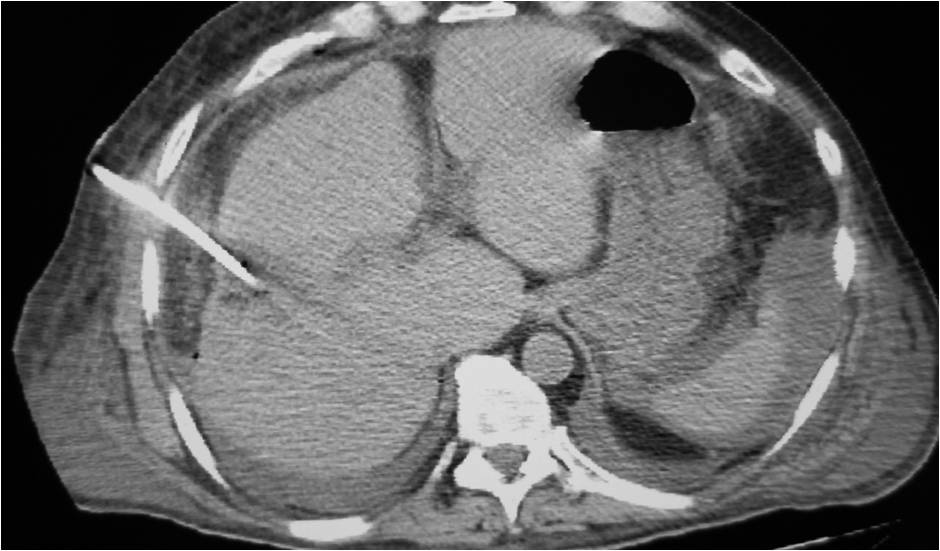

- Right sub diaphragmatic abscess post right hemicolectomy

- Successful drainage